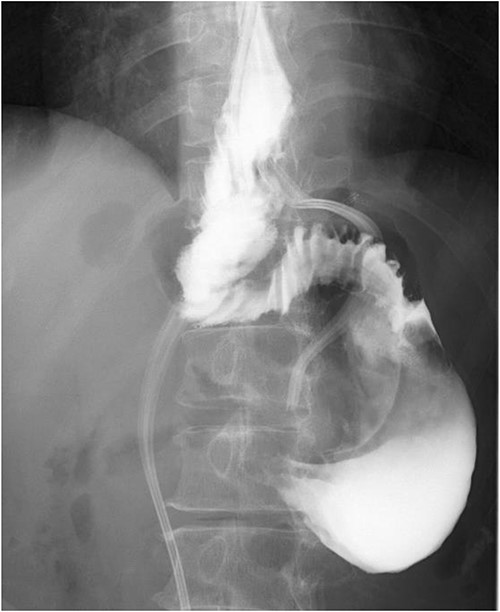

A 60-year-old female with dysphagia and vomiting visited the university hospital. In 2007, she underwent esophageal diverticulum resection (procedure unknown) with a diagnosis of an esophageal diverticulum, which subsequently recurred. In 2011, she underwent a transesophageal hiatus diverticulectomy and a fundoplication (Nissen procedure) at a local hospital. In 2013, dysphagia and vomiting appeared. The patient was diagnosed with recurrence and underwent balloon dilatation for follow-up. In 2015, the patient came to our hospital due to persistent symptoms. After one balloon dilation, the patient did not show any improvement and was referred for surgery. Esophageal fluoroscopy revealed a diverticulum 5 cm in size in the lower esophagus just above the eruption. There was no significant change in the diverticulum size before and after dilation (Figs 1 and 2). Gastrointestinal endoscopy revealed a diverticulum in the lower esophagus, with a residue accumulation (Fig. 3). The esophagus directly below the diverticulum was narrowed. The patient was diagnosed with recurrent lower esophageal diverticulum and underwent surgery.

Upper digestive tube endoscopy. The esophagus just below the diverticulum was stenotic, and there was residue accumulation in the diverticulum.